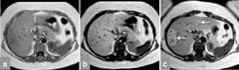

De aller fleste kontrastmidler som benyttes ved MR, er paramagnetiske (hvilket betyr at molekylene i kontrastmidlet blir magnetiske når de bringes inn i det kraftige magnetfeltet i en magnettomograf). Paramagnetiske stoffer kan påvirke T1-relaksasjonen og/eller T2-relaksasjonen til hydrogenkjernene i omkringliggende vannmolekyler, og dermed påvirke signalstyrken både i T1-vektede og T2-vektede MR-bilder. Hittil har man mest benyttet vannløselige, ekstracellulære kontrastmidler til intravenøs injeksjon. Disse fordeler seg i kroppen og utskilles helt analogt til de vanligste jodholdige røntgenkontrastmidlene. De viktigste indikasjonene er påvisning av tumor og inflammatoriske prosesser og bruk ved kontrastforsterket MR-angiografi (16), perfusjonsstudier og MR-artrografi. I de senere år har det imidlertid tilkommet mange nye kontrastmidler, og enda flere er under utvikling. Eksempler er leverspesifikke kontrastmidler som enten tas opp selektivt i hepatocyttene eller i kupffercellene (det retikuloendoteliale system) (fig 7), lymfespesifikke kontrastmidler (tas opp i lymfeknuter), intravaskulære kontrastmidler som holder seg i blodbanen (spesielt for MR-angiografi og perfusjon) og tumorspesifikke kontrastmidler (foreløpig på eksperimentstadiet). Det arbeides også med såkalte hyperpolariserte gasser, som er magnetiserte edelgasser (xenon, helium). Disse kan bl.a. utnyttes til MR-avbildning av bronkialtre og lunger, med en detaljoppløsning som langt overgår scintigrafi.